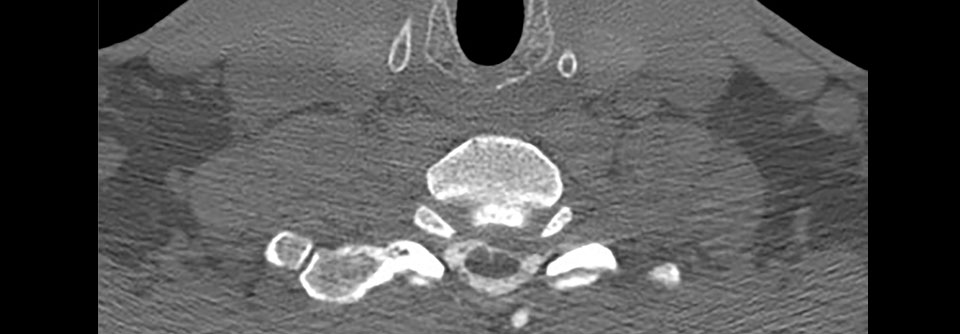

Zervikale Diskusläsion

Hinweise auf die Genese in der Bildgebung oft eindeutig zu erkennen

Meist stecken hinter einer zervikalen Diskusverletzung degenerative Prozesse. Wer rechtsmedizinisch beurteilen muss, ob es sich um eine unfallbedingte…

Orthopädie